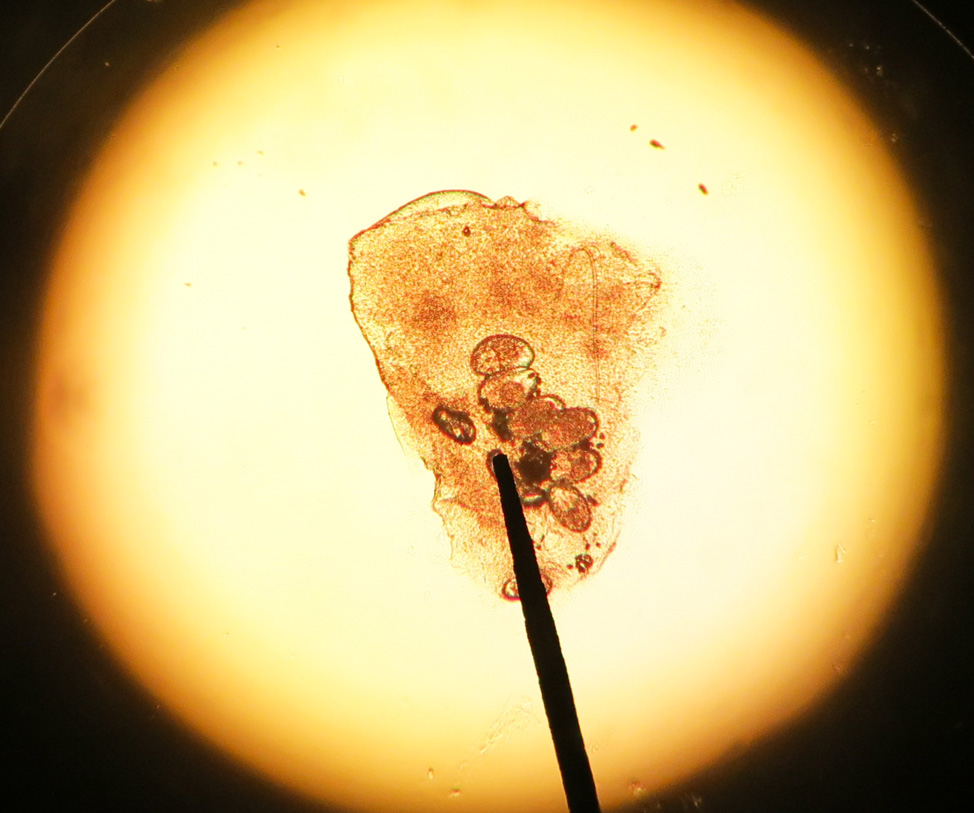

Nail Disorders – There are several different diseases that affect the nails, often as a result of a fungal or bacterial infection. Ingrown toenails are the most common nail ailment, involving the corners of the nails digging into the surrounding soft tissue, causing irritation and swelling. Fungal infections commonly affect the toenails (and sometimes the fingernails as well), as a result of exposure to a warm, moist environment, and cause thick, brittle and distorted nails.

Treatment for nail diseases may include oral or topical medications. The nail may need to be removed for severe infections. Patients can prevent nail conditions from developing by keeping the feet clean and dry, wearing shoes that fit well and clipping toenails straight across.